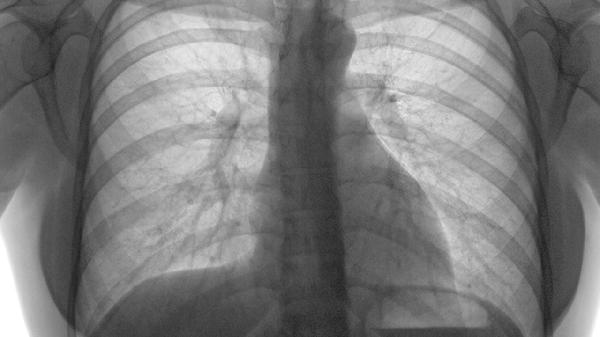

核素肺通气灌注扫描通过比较通气与血流分布不匹配区域辅助诊断。典型表现为灌注缺损而通气正常。该检查适用于造影剂过敏或孕妇等特殊人群,但结果需结合临床概率评估。

超声心动图可发现右心室负荷过重的间接征象,如右室扩大、室间隔左移等。床旁超声对血流动力学不稳定的高危患者具有快速评估价值,但无法直接显示肺动脉血栓。